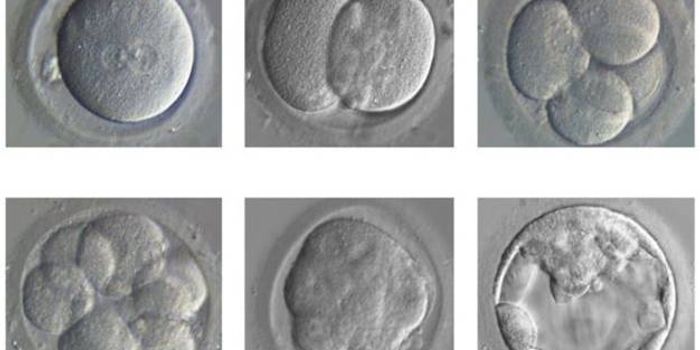

FEB 02, 2016Clinical & Molecular DXIn a historic, unprecedented move, UK national fertility regulators have given the green light for scientists to use the ...

FEB 25, 2016Clinical & Molecular DXCellular reprogramming has been a hot topic in translational and regenerative medicine ever since it was first described ...